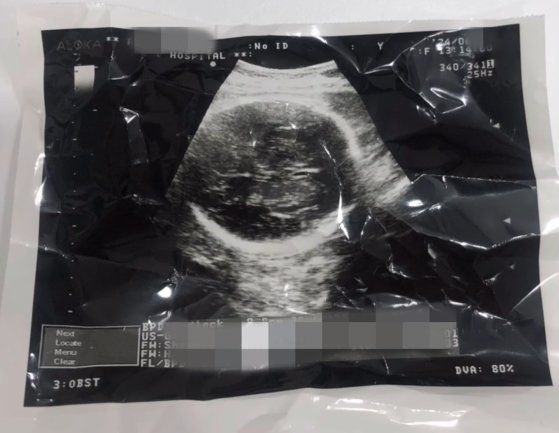

36주차 낙태 의혹이 불거진 영상 관련 태아 초음파 사진 캡처. 사진 인스타그램

경찰은 영상에 담긴 태아 초음파 사진도 중요한 단서로 봤다. 초음파 사진에서 촬영 날짜와 출산 예정일 등 의료 정보를 확인하고, 산부인과 의사 등에 대한 참고인 조사를 진행해 A씨 본인 주장과 같이 임신 36주차에 해당한다고 봤다. 영상에선 산부인과 관계자로 추정되는 한 여성이 “이 정도면 (아이를) 낳아야 한다. 심장이 잘 뛰고 있다”고 언급하기도 한다.